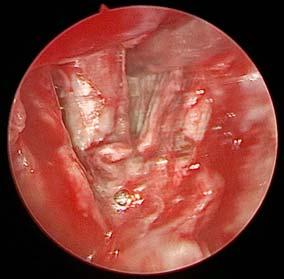

Punch biopsy from the oral cavity especially the necrotic palatal part and/or collection of infected tissue/ nasal discharge is/are sent for (KOH test) to screen for any fungal hyphae. KOH test is a rapid method of identifying the presence of fungal hyphae or yeast compared to the fungal culture which takes weeks for reporting and thus was done for all our patients. Histopathologic examination as well as fungal and bacterial culture were also done from the tissue samples. From surgical debridement to maxillectomy (partial, subtotal, total) till orbital exenteration, the surgical intervention varies depending on the orbital involvement.